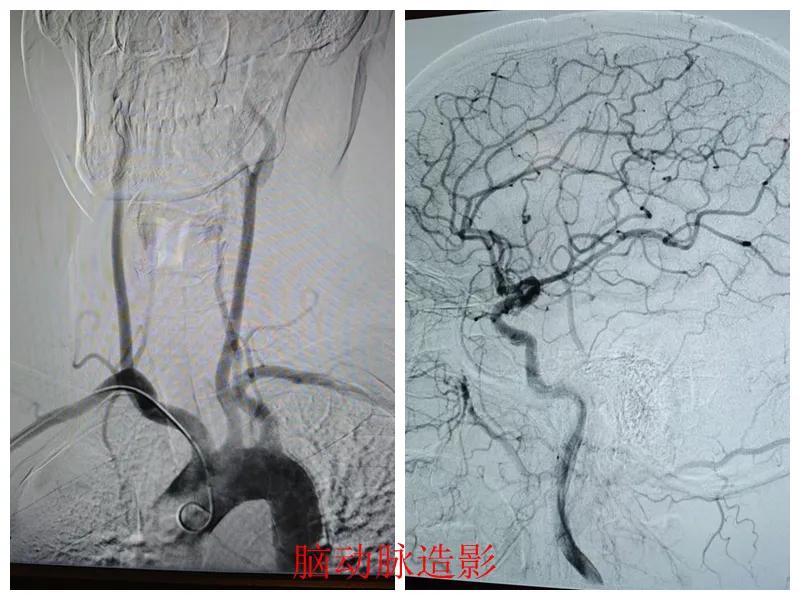

術(shù)前準(zhǔn)備完善后,在王瑾院長帶領(lǐng)下,心血管內(nèi)科主任李慧新、影像科主任宋貴良、副主任醫(yī)師趙進(jìn)科等緊密協(xié)作,成功為患者實(shí)施了冠狀動脈造影及腦動脈造影兩項(xiàng)檢查。冠狀動脈造影結(jié)果提示:患者右冠狀動脈慢性閉塞,腦動脈造影提示腦血管多支狹窄病變。